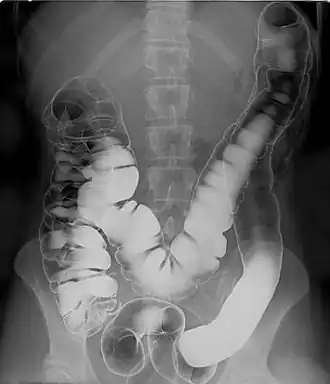

The hepatic and splenic flexures labelled at either side of transverse colon

In the anatomy of the human digestive tract, there are two colic flexures, or curvatures in the transverse colon. The right colic flexure is also known as the hepatic flexure, and the left colic flexure is also known as the splenic flexure.[1]

The right colic flexure or hepatic flexure (as it is next to the liver) is the sharp bend between the ascending colon and the transverse colon. The hepatic flexure lies in the right upper quadrant of the human abdomen. It receives blood supply from the superior mesenteric artery.

The left colic flexure or splenic flexure (as it is close to the spleen) is the sharp bend between the transverse colon and the descending colon. The splenic flexure receives dual blood supply from the terminal branches of the superior mesenteric artery and the inferior mesenteric artery.[2]